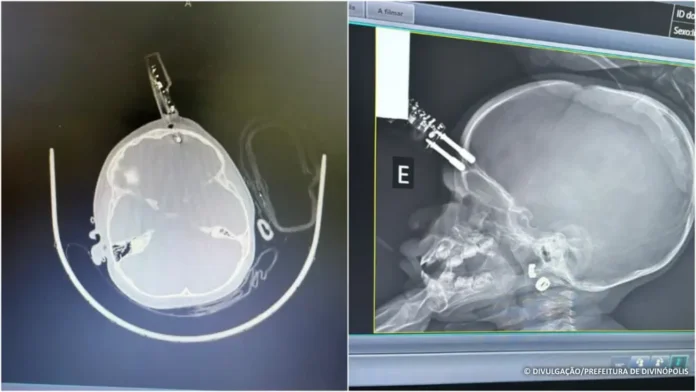

Os exames de tomografia revelaram que o pino havia atingido a ponta do lobo frontal do cérebro. A criança passou por uma cirurgia de emergência para remoção do objeto. Segundo o neurocirurgião responsável pelo caso, Dr. Bruno Castro, o procedimento foi rápido, tranquilo e sem intercorrências. Os médicos estancaram o pequeno sangramento e corrigiram a falha no crânio. A menina permaneceu 36 horas em observação no CTI pediátrico.